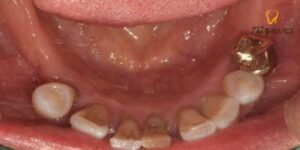

육안으로 먼저 살펴 보았더니 환자분 말씀처럼

구치부가 다수 상실되어 있고

여러 치아도 흔들리고 있었으며,

특히 하악 어금니가 상악 어금니를

받쳐주지 못해 정출되어 있었습니다.

상악의 우측의 경우 아래쪽에

대합되는 구치부가 상실된 지 오래되어

소구치와 대구치 모두 정출되어 있었는데요.

두 치아는 보존하기 어려워

발치를 진행한 후 수암동치과 임플란트를

진행하기로 하였습니다.